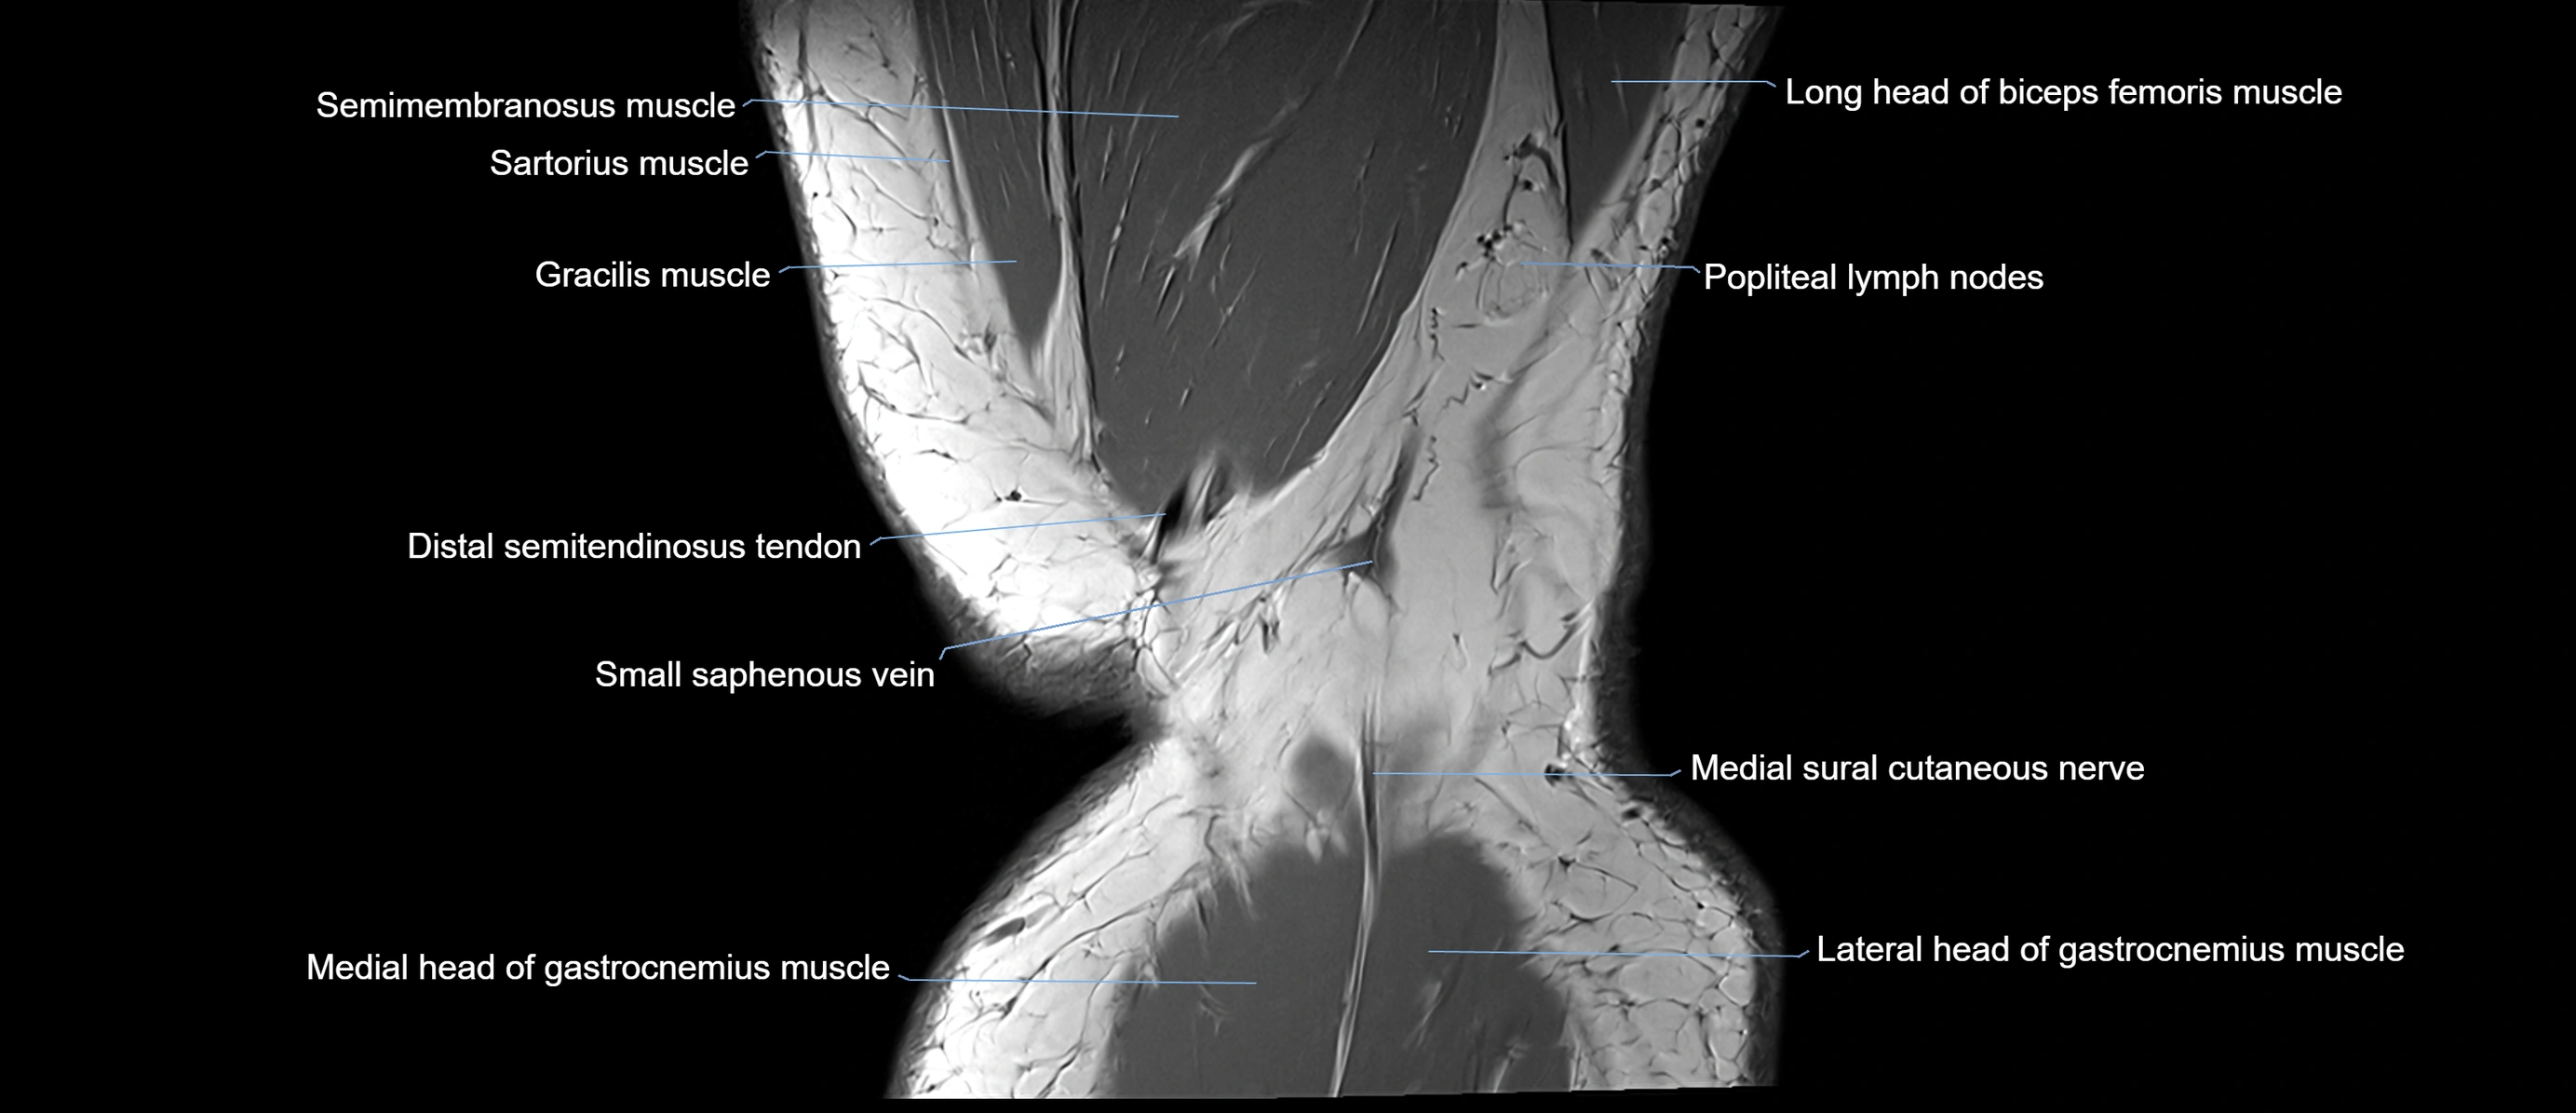

- Biceps femoris muscle (Long head)

- Distal semitendinosus tendon

- Medial head of gastrocnemius muscle

- Medial sural cutaneous nerve

- Popliteal lymph nodes

- Semimembranosus muscle

- Small saphenous vein